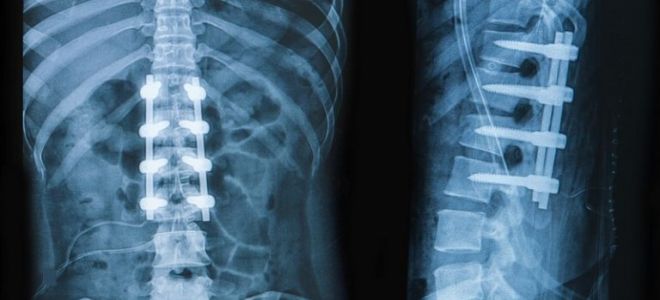

- Снижение числа шейных позвонков, что приводит к укорочению этого сегмента осевого скелета. Позвонки могут срастаться друг с другом, что изменяет их нормальную подвижность. Эти изменения хорошо видны на рентгеновских снимках.

Постановка диагноза начинается с осмотра пациента, в ходе которого выявляются характерные видимые аномалии в строении шейного отдела позвоночника. Наличие дополнительных деформаций осевого скелета или неврологических симптомов также может свидетельствовать о развитии заболевания. Для подтверждения диагноза применяются визуальные методы. Рентгенография является наиболее доступным способом диагностики синдрома Клиппеля-Фейля. Снимки выполняются в двух проекциях, при этом боковая проекция считается наиболее информативной. Однако полученные изображения не позволяют оценить состояние спинного и головного мозга. Для визуализации этих структур используются компьютерная и магнитно-резонансная томография. В большинстве случаев такие исследования обязательны, так как их результаты необходимы как для прогнозирования течения заболевания, так и для подготовки к оперативному вмешательству. Прежде чем начать лечение, также важно оценить функции внутренних органов, что связано с высокой вероятностью наличия сопутствующих аномалий. Для этого проводятся ультразвуковые исследования, а также анализы крови и мочи.